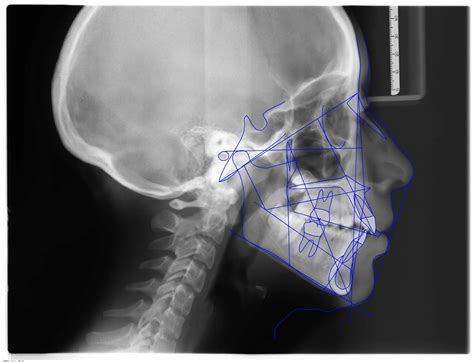

La telerradografía lateral de cráneo inicial (fig. 5) evidencia el resalte existente, con una mandíbula que presenta características típicas de tener un buen potencial de crecimiento.

Figura 5. Telerradiografía lateral de cráneo pretratamiento.

Cefalométricamente, según Ricketts (fig. 6), encontramos un patrón mesofacial, con una maloclusión esquelética de Clase II de origen mandibular, con incisivos inferiores retroinclinados.

Figura 6. Trazado cefalométrico pretratamiento.